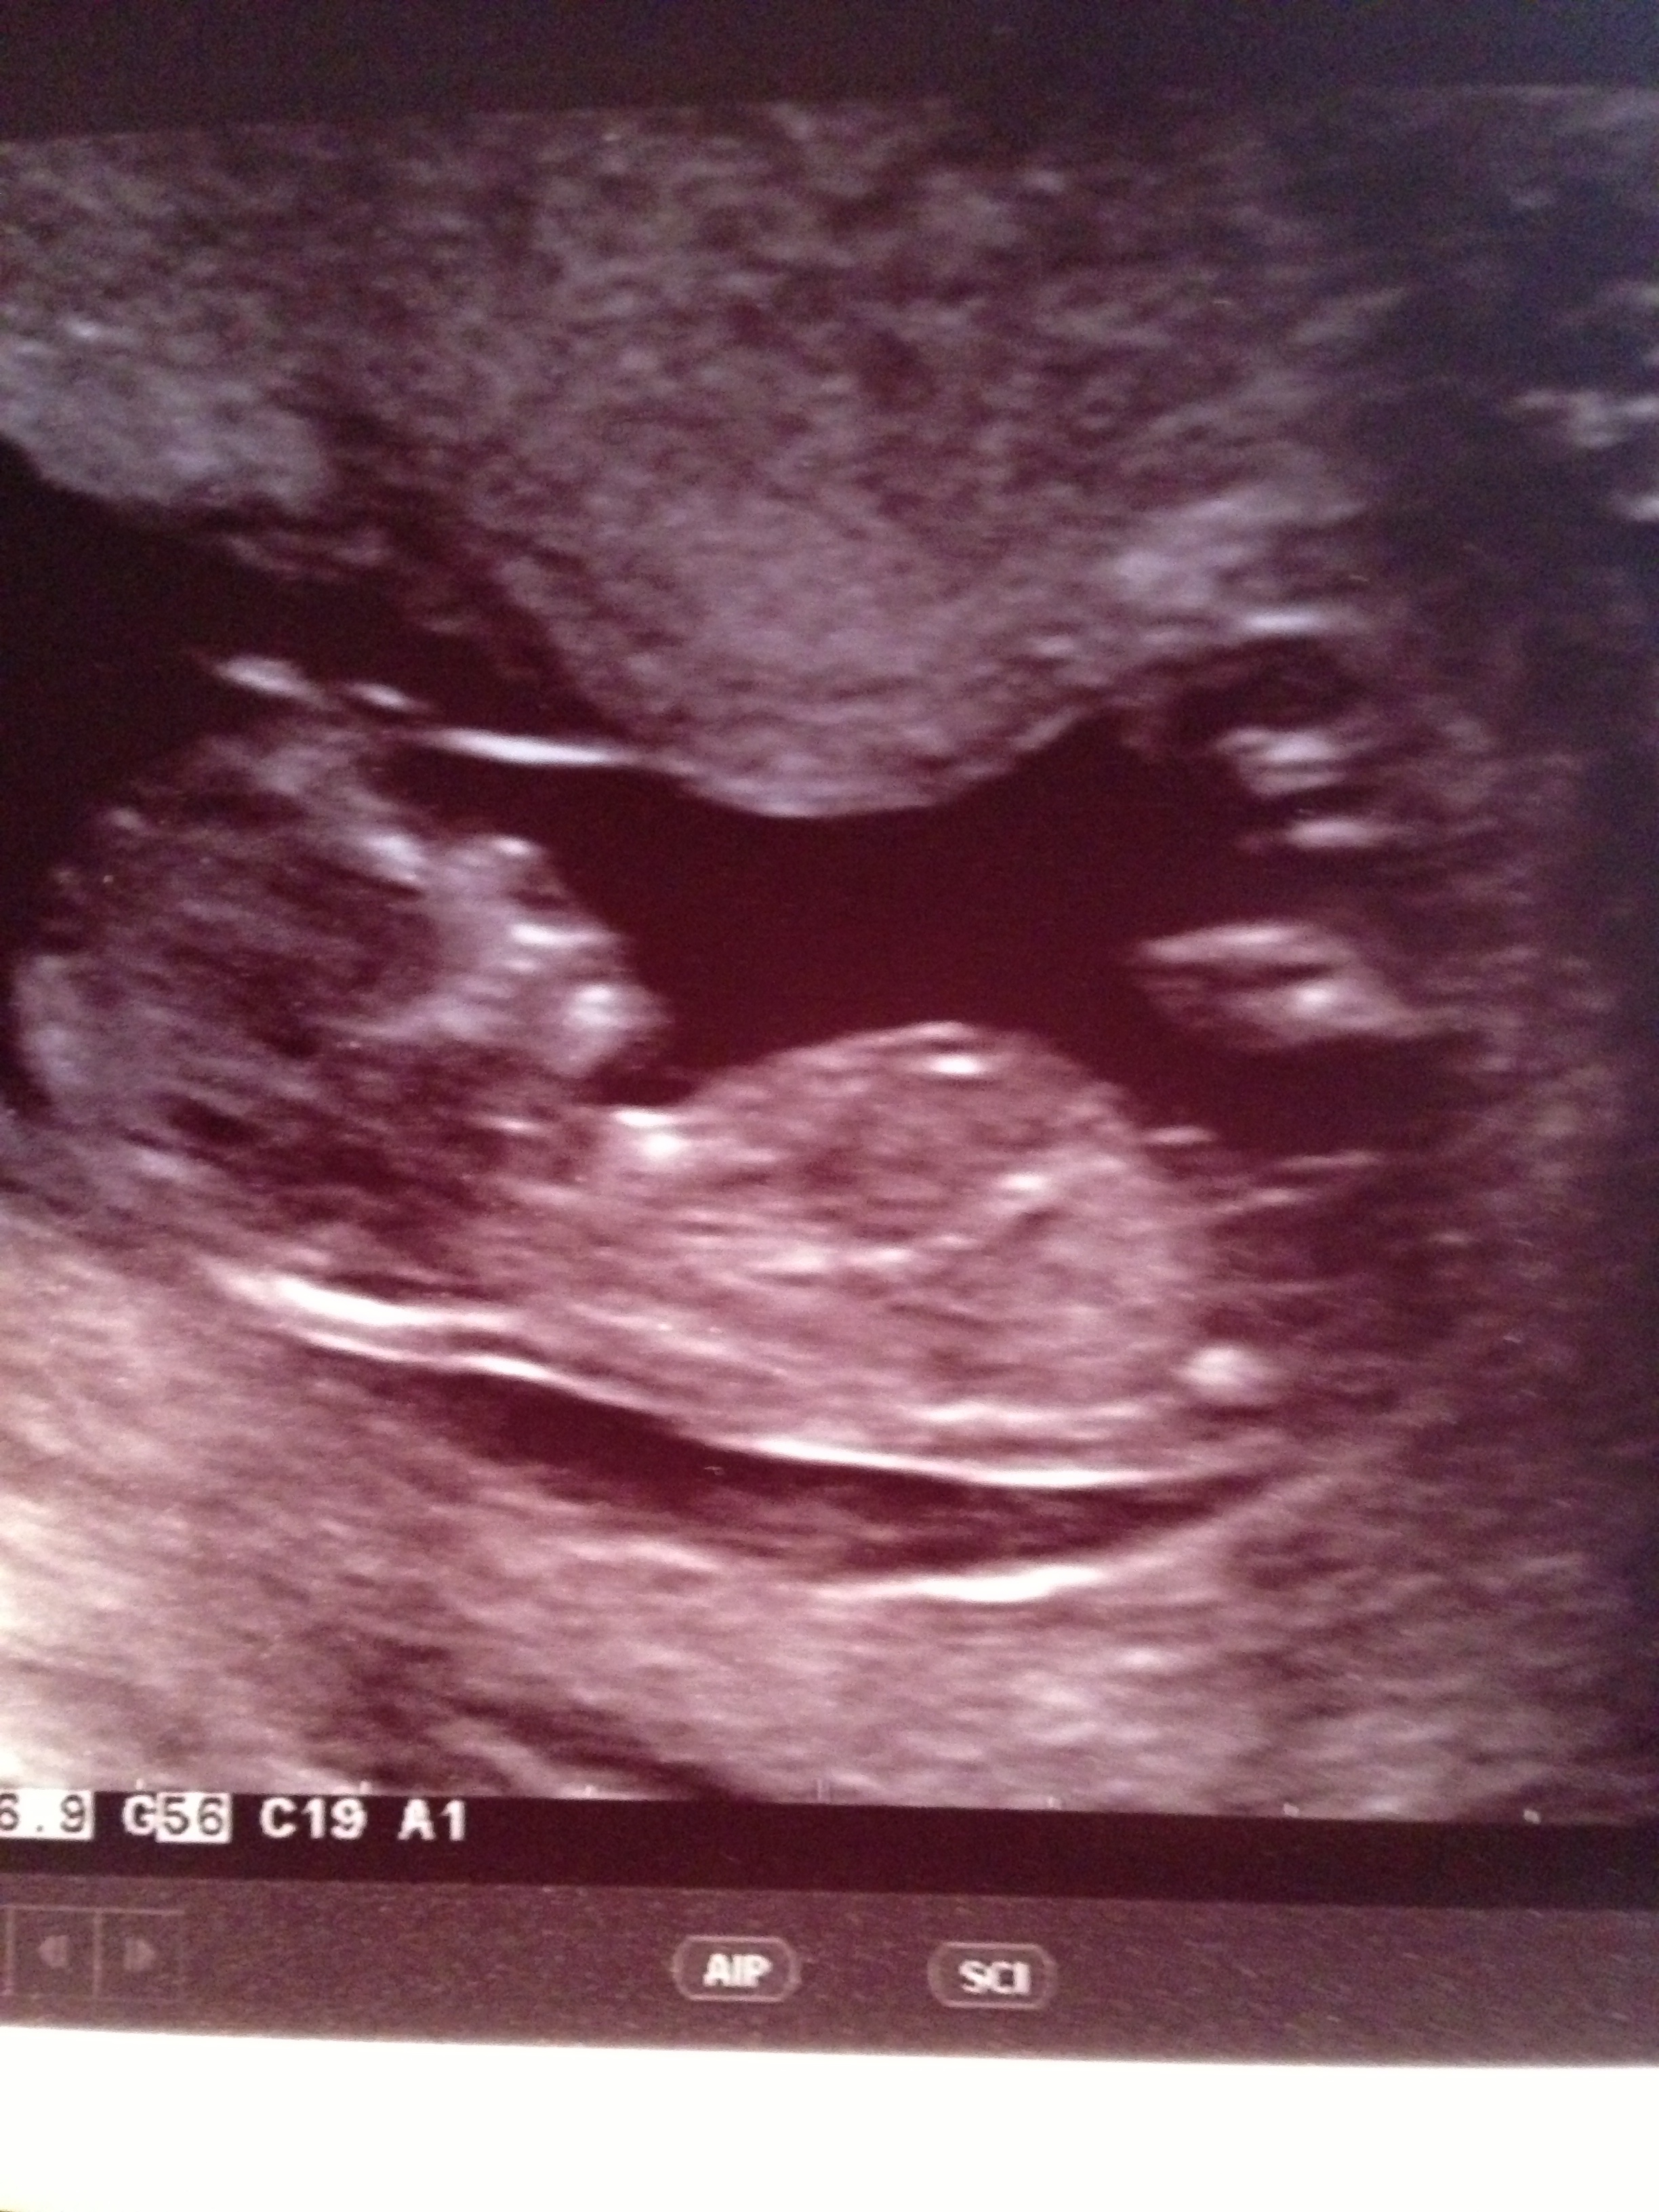

This is my 13 week scan - has anyone got any idea on gender? I have no idea which is the nub if there is one visible. Many thanks!

There may be a faint girl nub. Above that is cord.

lovemy4 - so just because I'm stupid at these things, the longer line is the cord, then you think the faint line below that is nub and then there's a kind of bright blob below that which is nothing of importance?